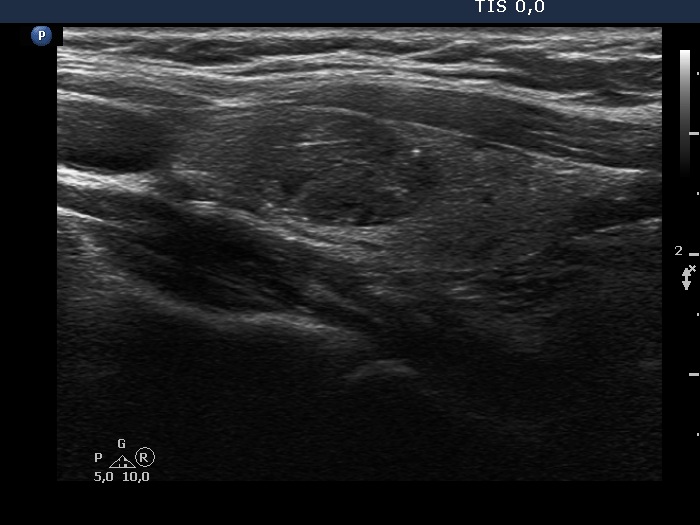

Right lobe, longitudinal scan

Right lobe, longitudinal scan. The echogenic figures involve both lines and granules. These are probably back wall figures.